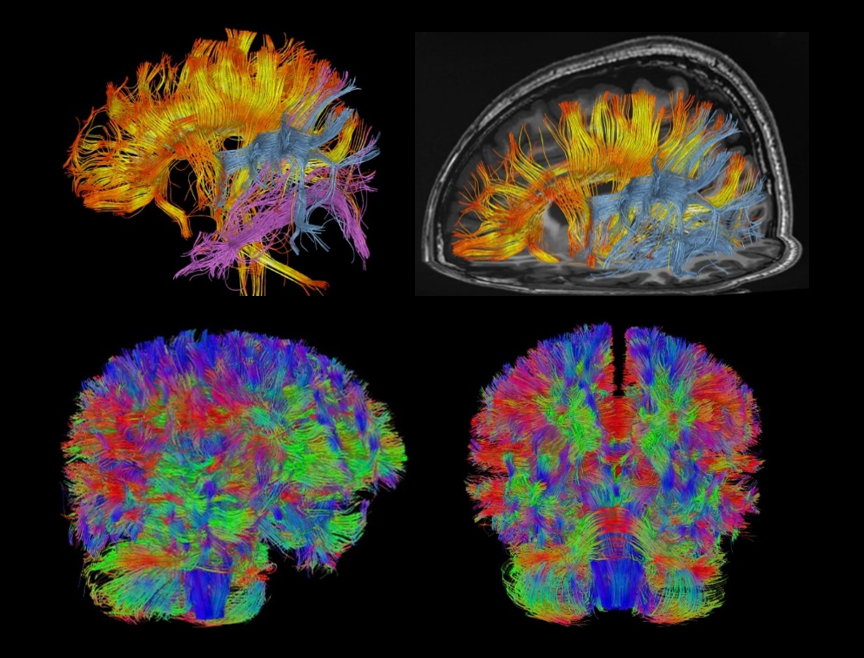

Galerie clinică

DTI cu 256 direcții pentru cap